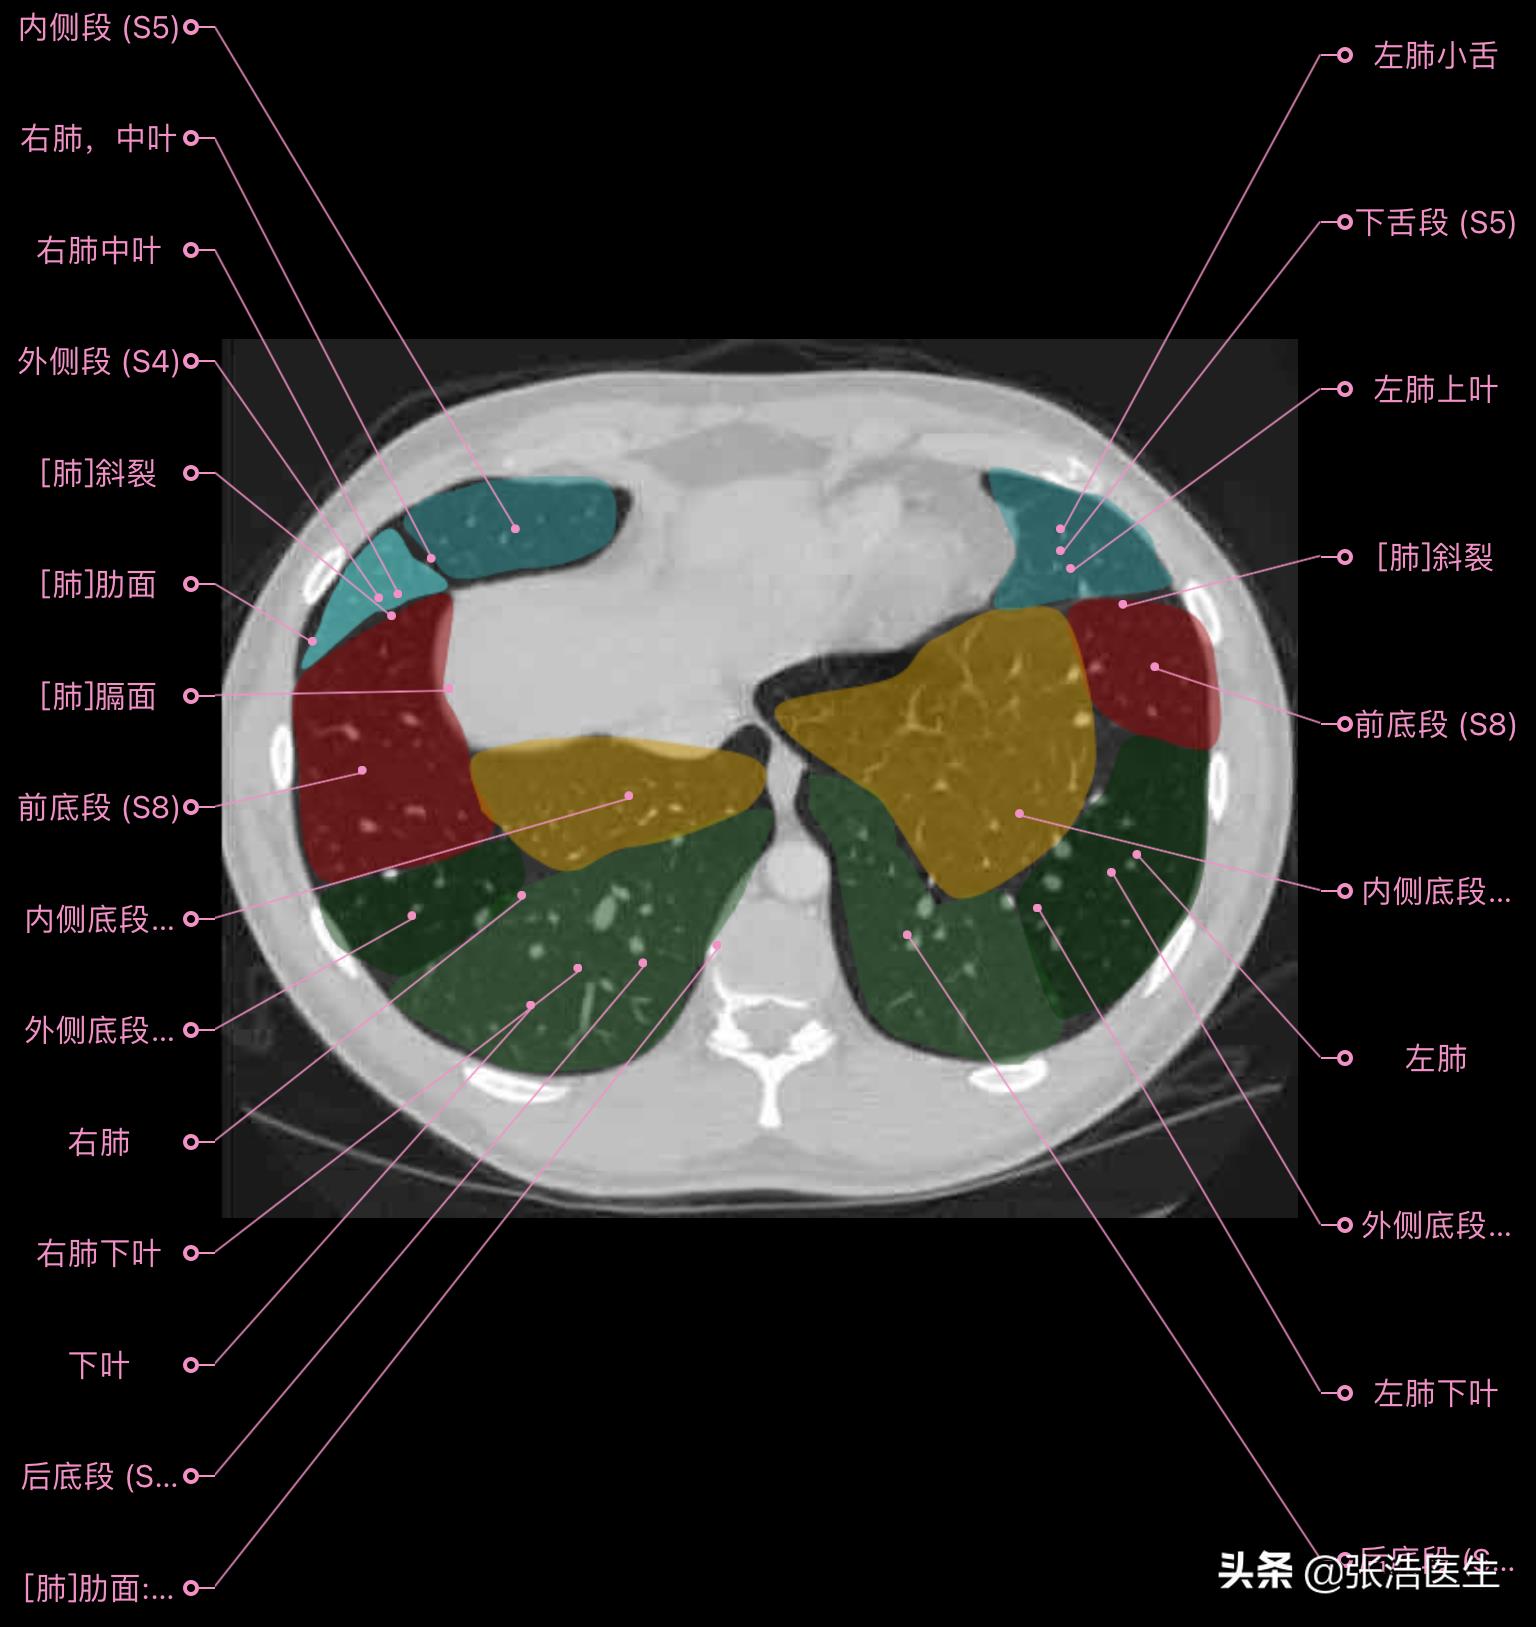

肺部CT横断面高清解剖图谱(图层4)